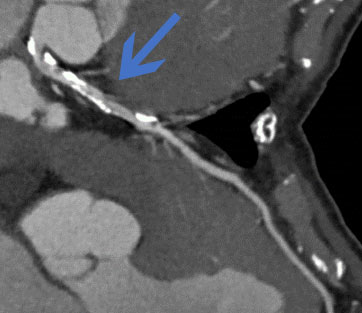

冠動脈CT検査

突然死の原因の1つである心筋梗塞のリスクとなる病変の早期発見に有効です。